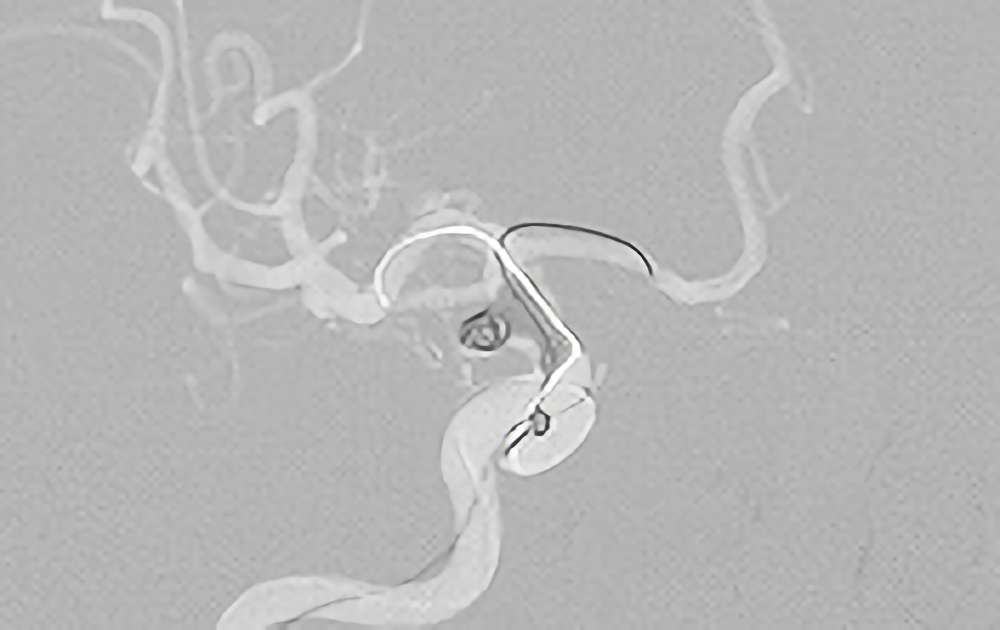

No.1630 手術前